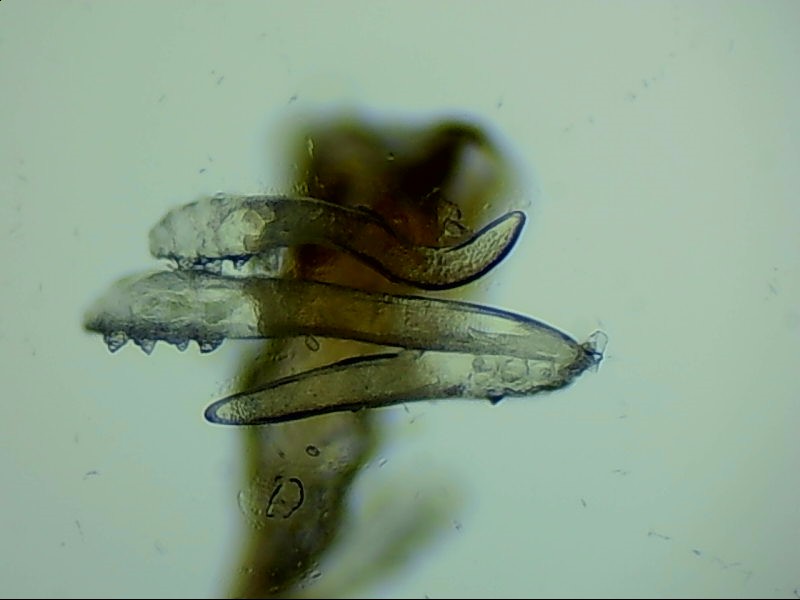

蠕形螨是螨蟲的一種,主要寄居在毛囊中。蠕形螨以分泌的油脂、分泌物為食,所以眼部寄居著蠕形螨的患者多有亂睫或睫毛脫落的癥狀。

蠕形螨寄居后,它們以睫毛毛囊里面的油脂為食。隨著油脂的缺失,睫毛會長的東倒西歪,如果毛囊里的油脂都被吃光了,就會出現(xiàn)睫毛脫落這種蠕形螨性瞼緣炎的典型癥狀。

身體健康時(shí),蠕形螨就吃吃油脂,夜里爬出來活動、交配,與我們相安無事,一旦身體的免疫力下降,蠕形螨的活動、產(chǎn)的卵、排泄的廢物和分泌的分泌物都會引起過敏反應(yīng)?;颊邥霈F(xiàn)眼癢、異物感、眼干、瞼緣充血、鱗屑、睫毛根部袖套狀分泌物及睫毛脫落等癥狀,嚴(yán)重者可并發(fā)結(jié)膜及角膜病變,給生活帶來不便和困擾。